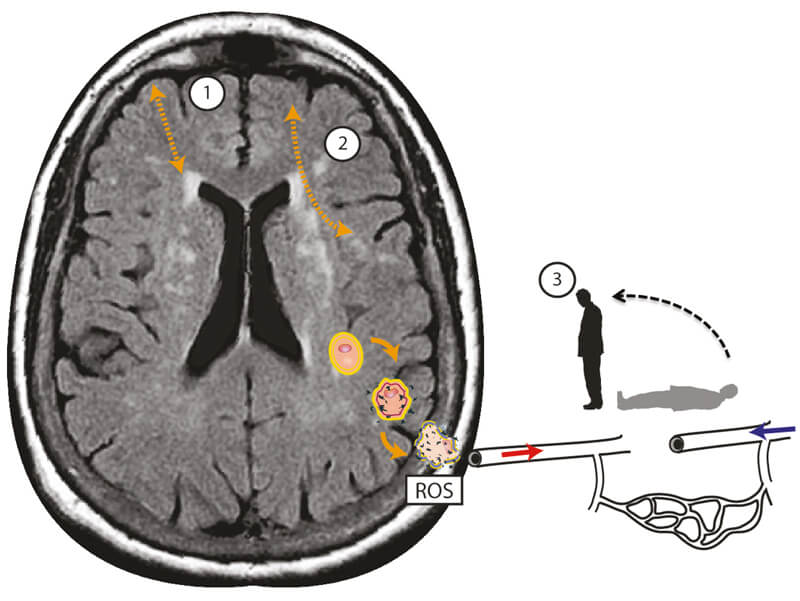

Figure 1. Schematic representation of the additional deleterious effects of postural blood pressure hypotension in cerebral small vessel disease associated dizziness in addition to cortico-subcortical (1), and cortico-cortical (2) disconnectivity. Localised oxidative stress processes damage the cerebral vasculature, leading to endothelial dysfunction and promoting neurodegenerative alterations in the brain tissue through reactive oxidative species (ROS). Microvascular endothelial dysfunction in turn disrupts cerebral autoregulation - which, in healthy states, maintains adequate and stable cerebral blood flow when blood pressure drops. This leads to intra-cerebral orthostatic hypotension and perfusion, manifest as postural light-headedness and imbalance.

Reprinted from Kaski et al [4] with permission from Elsevier.

This sort of distributed function is at risk of disruption by cSVD which affects multiple connections in many areas at once. Loss of connectivity by age-related build-up of cSVD could lead to dizzy feelings through one or more of the following mechanisms (see Figure 1): disconnection of cortical vestibular centres, disconnection between frontal gait centres and the basal ganglia, and disconnection between intended motor action (efference copy) and ascending sensory inputs (sensory re-afference). In addition, we propose that cSVD-mediated dysregulation of cerebral blood pressure is linked to dizziness during standing and walking, explaining why measurement of postural blood pressure in the arms is usually normal in these patients [4].